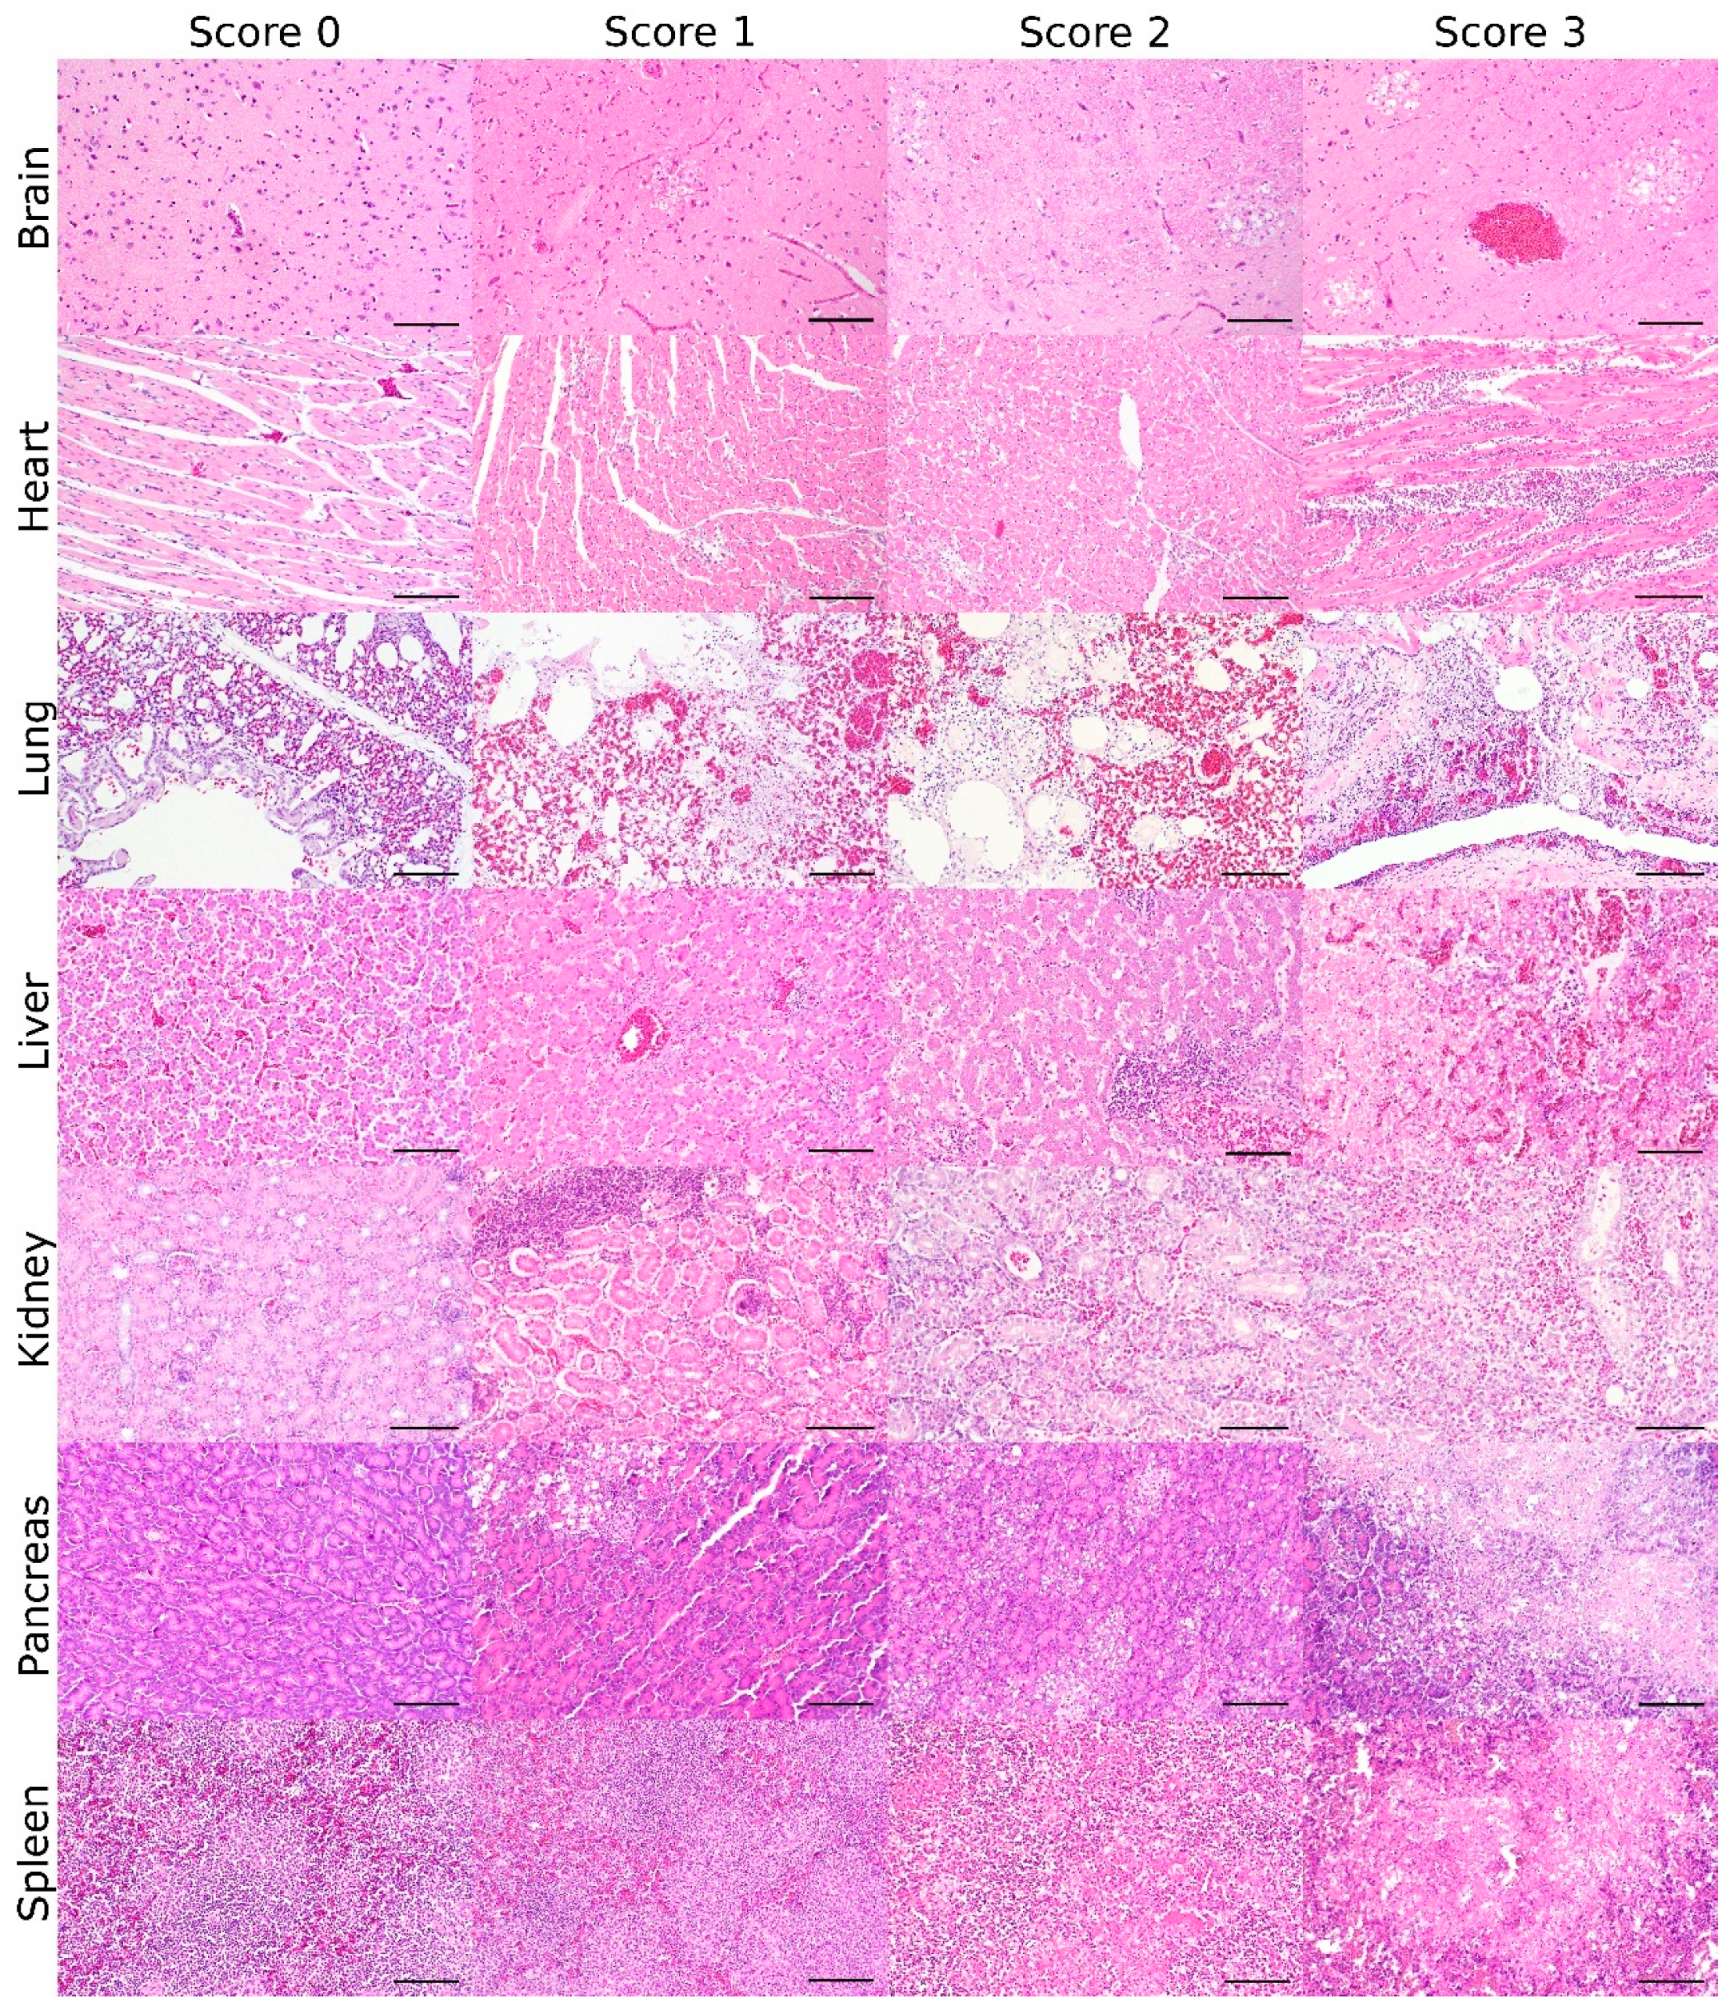

The proposed scoring system focuses on the assessment of the brain, heart, liver, kidney, lung, pancreas, and spleen, as they represent the great parenchymal organs and lymphoid tissues mainly affected. Scoring criteria are defined and illustrated for those organs in Table 1 and Figure 1.

Figure 1.

Lesion score: Histopathologic scoring of the grade of avian influenza virus (AIV)-induced necrotizing lesions and lymphoid depletion in AIV-infected birds (bar = 100 µm, hematoxylin and eosin).